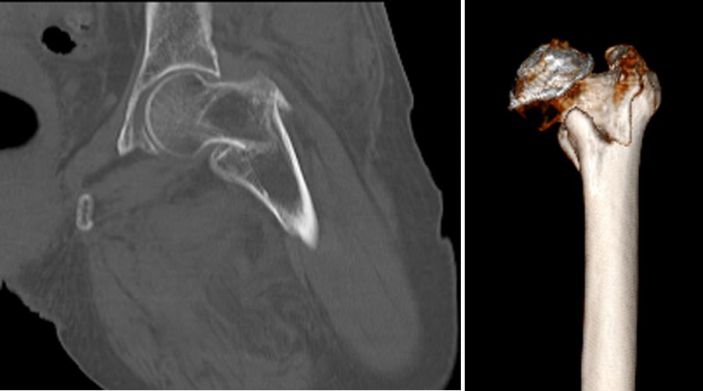

吳志斌主任通過CT+三維重建先行拟定詳細手術方案,提前做了精心準備。根據患者的年齡特征,爲其選擇最佳的半髋置換方案,并采用雙動人工股骨頭,提高活動範圍,減少髋臼磨損。

△術前